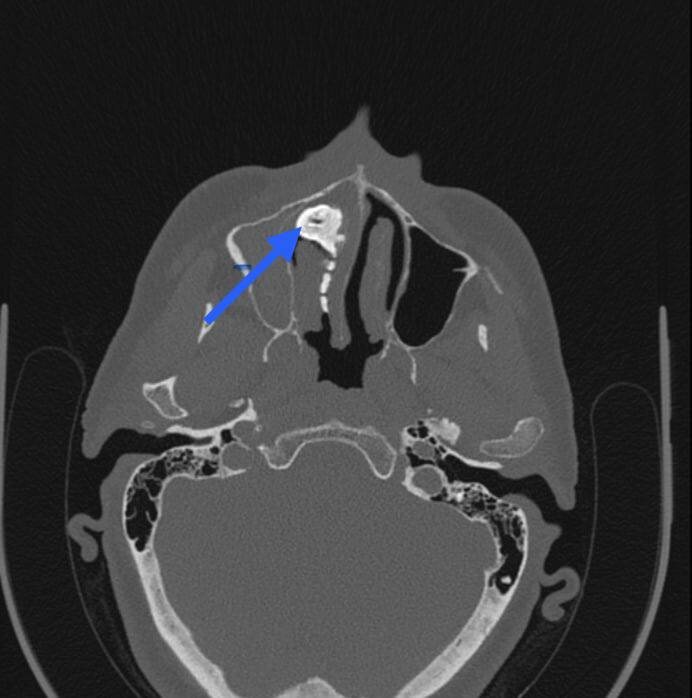

Ринолит размером с перепелиное яйцо

Это оказался ринолит или, так называемый, носовой камень. Он образуется в результате длительного ослизнения инородного тела. Процесс не быстрый, длится месяцами и годами. А судя по размеру данного ринолита, он был с перепелиное яйцо, это заняло далеко не один год.